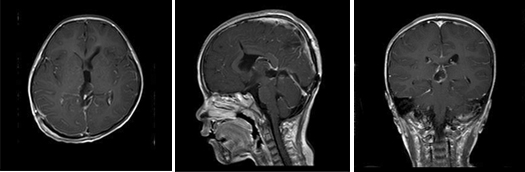

小刘在4月份的某一天上午上学时突然出现头疼,老刘赶紧带着孩子到当地医院就诊,给予对症处理,可是小刘还是感觉不舒服,结果没几天,小刘感觉头疼加重伴有呕吐,慢慢的变得意识模糊,老刘紧急送往当地儿童医院就诊,医生通过CT检查发现小刘为松果体及三脑室占位病变,梗阻性脑积水,给予脱水,降颅压,紧急行右侧侧脑室钻孔外引流术,术程顺利,术后给予相应治疗后小刘慢慢的神志清醒,头疼症状缓解,未再出现呕吐,老刘一家为了让小刘更好得康复,于是转院到广东三九脑科医院神经外七科进行治疗,神经外七科吾太华主任在详细了解小刘情况后,根据复查颅脑CT提示松果体及三脑室内占位病变,脑积水脑室外引流术后改变,遂以“松果体及三脑室占位,梗阻性脑积水”收治入院,入院后完善相关检查,进一步明确诊断,颅脑MR检查提示为松果体及三脑室内占位病变,考虑生殖性肿瘤,以成熟型畸胎瘤可能性大,幕上梗阻性脑积水脑室外引流术后改变,经积极术前准备,小刘在全麻下性松果体及三脑室内占位病变切除术,术程顺利,术后病理为松果体及三脑室不成熟畸胎瘤 WHO I级,复查颅脑MR提示原病变已切除,颅脑CT提示脑积水已缓解。

术后影像检查